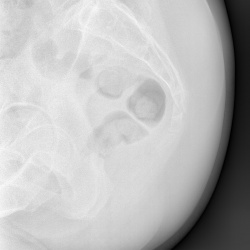

Добрый день. Подскажите пожалуйтса как описать в нижних отделах левого легкого.. как образование слева ?